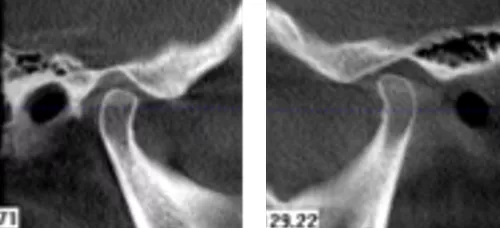

· 双侧髁突骨皮质连续。

· 修复体戴入后髁突位于关节窝内的适中位置。

· X线片显示,种植体周骨稳定性、关节髁突位置评估均无异常。